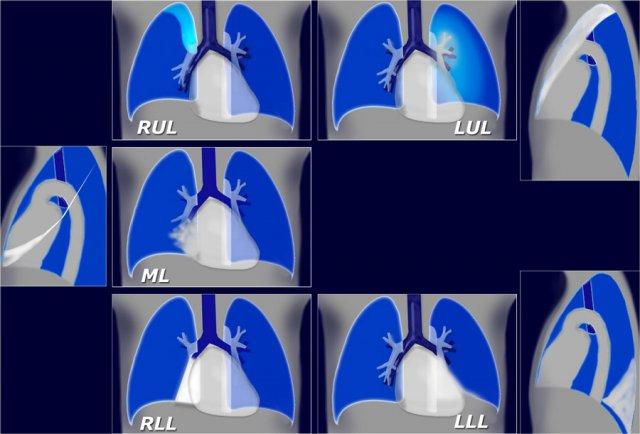

Xẹp thùy phổi

Xẹp thùy phổi là một phát hiện quan trọng trên X-quang ngực và có chẩn đoán phân biệt giới hạn.

Các nguyên nhân phổ biến nhất gây xẹp phổi bao gồm:

- Ung thư phế quản ở người hút thuốc lá

- Nút nhầy ở bệnh nhân thở máy hoặc bệnh nhân hen phế quản (ABPA)

- Ống nội khí quản đặt sai vị trí

- Dị vật đường thở ở trẻ em

Đôi khi xẹp thùy phổi chỉ gây mất thể tích nhẹ do ứ khí bù trừ ở các phần phổi còn lại.

Hình minh họa tóm tắt các dấu hiệu của các thể xẹp thùy phổi khác nhau.

Xẹp thùy trên phổi phải